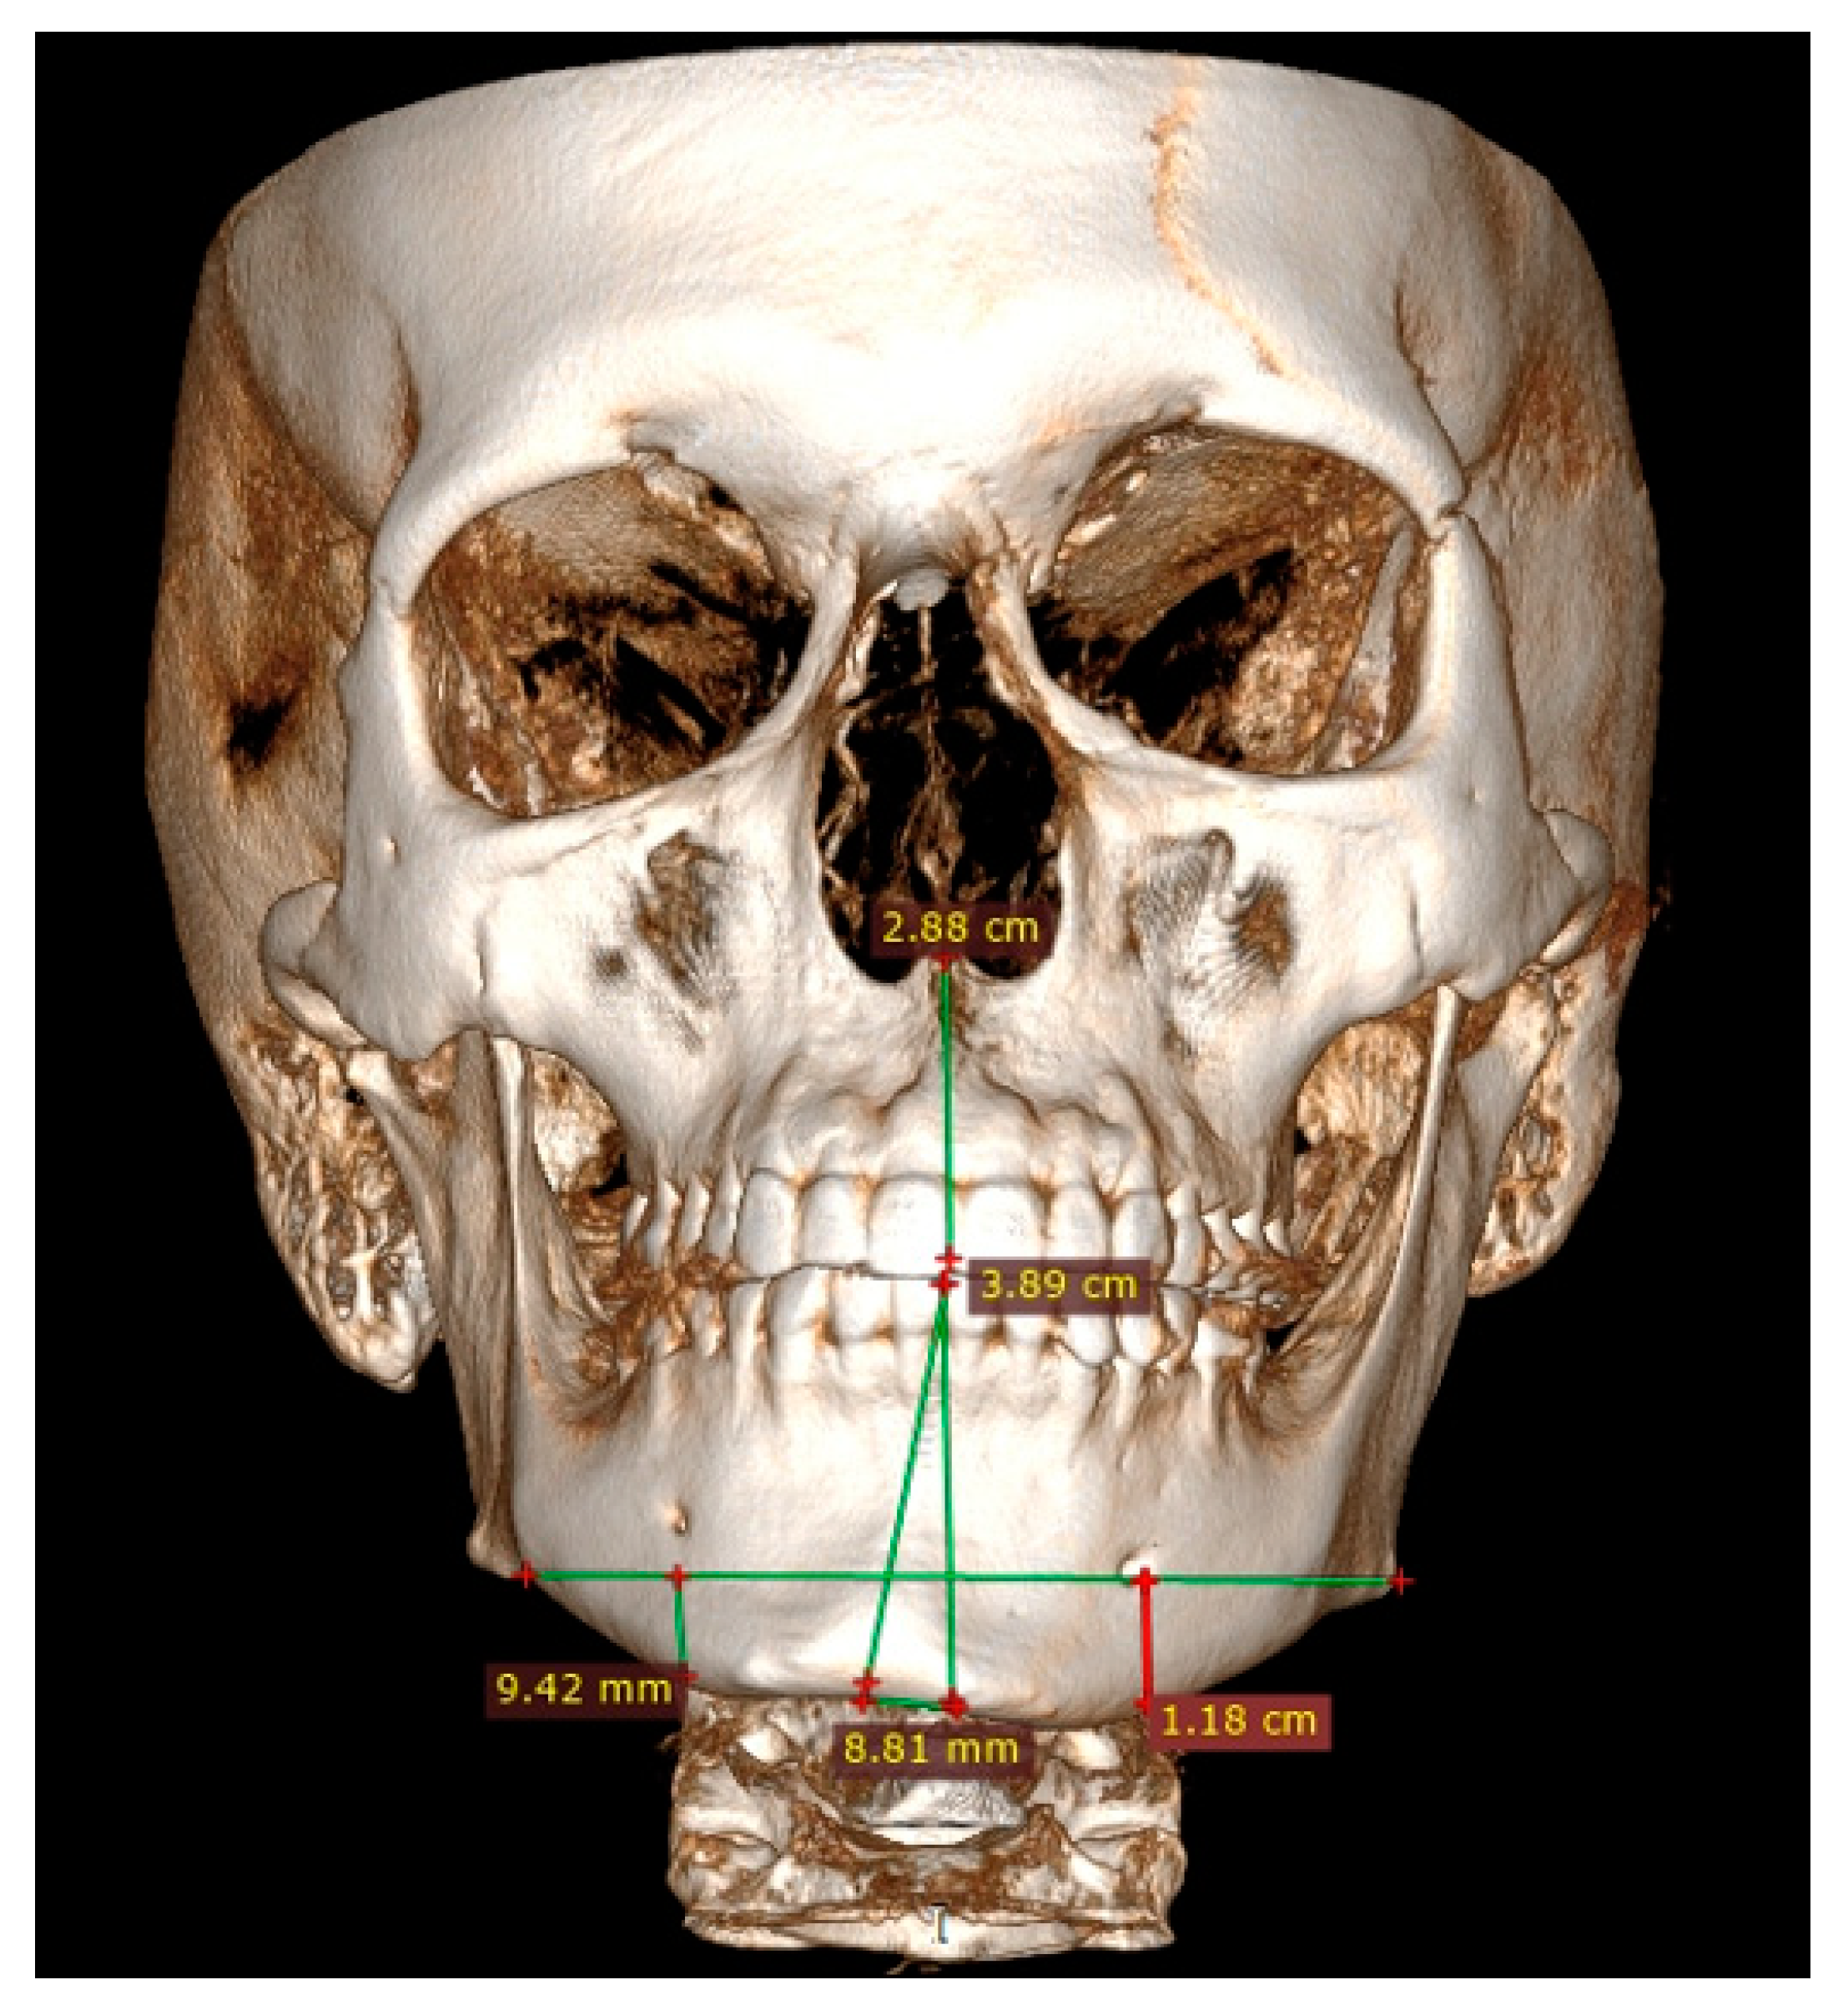

3.4. Low-Dose Computer Tomography

Both panoramic radiographs and LDCT evaluations are important for any surgery planning. There is a possibility to estimate the shape and position of the mandibular canal while tracing its course on 3D evaluation and then estimating the degree of surgery in MIB (Figure 3 and Figure 4). Secondly, based on the studied patients’ data, the authors also include that the position of the mental foramina, chin deviation, and Go reference points described herein are valuable reference points for future surgical planning. Another important feature possible to estimate on 3D-LDCT is the scope of mandibular basis overgrowth in three dimensions.

Figure 3.

LDCT—evaluation in low-dose CT focused on central symmetry line and differences in measurements between mental foramina, MIB, chin position, and mandibular angle contour.

The usage of a 2D-panoramic radiograph is helpful. More important measurements nowadays are made on 3D-virtual planning models (Figure 5). 3D planning might improve surgeons’ insight and the scope of bone evaluation. Because of great improvements in surgical planning, not only 3D-CT/LDCT evaluation is helpful. The usage of 3D stereolithographic models is an alternative method, where surgical cuts and plate bending might be quite easily made before surgery to ensure that the selected surgical approach is the most adequate of all. In cases of asymmetry visualized in patients in face view after orthognathic, surgical, and orthodontic treatment, some detailed total mandibular symmetry correction protocols are needed. Direct 3D-LDCT planning based on the used anatomical reference points presented herein is helpful in restoring facial balance and mandibular symmetry (Figure 6 and Figure 7). The authors’ future studies will focus on the 3D evaluation of facial skeleton, soft tissue changes in CT/MR, and lateral profile alterations; because of that, any other data are excluded from this study.

Figure 5.

Patient CT evaluation after BSSO. Presented frontal scan underlines still present asymmetry in the left mandibular basis, which was not fully camouflaged after BSSO and required further surgical approaches for definitive mandibular symmetry correction.